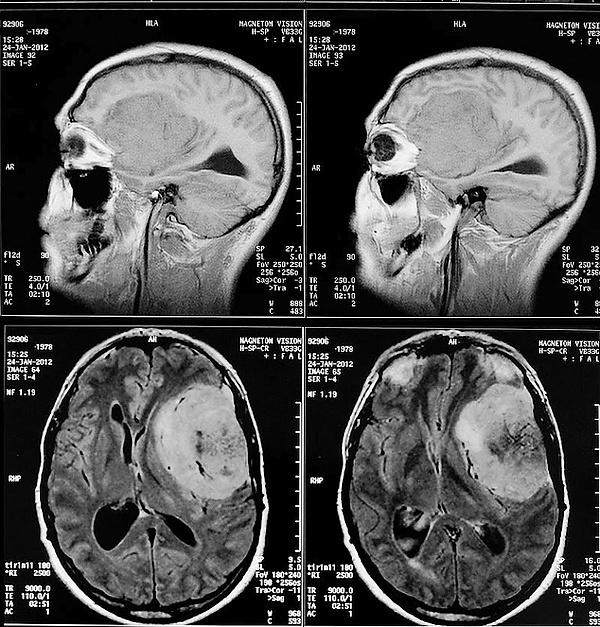

Для диагностики менингиом используются следующие методы нейровизуализации: МРТ, КТ, ПЭТ, селективная и неселективная церебральная ангиография, сцинтиграфия.

В настоящее время МРТ с контрастным усилением является ведущим методом диагностики менингиом практически любой локализации. МРТ позволяет визуализировать васкуляризацию опухоли, степень поражения артерий и венозных синусов, а также взаимоотношения между опухолью и окружающими структурами. На нативных T1-взвешенных МРТ большинство менингиом не отличаются по интенсивности от коры головного мозга. Фиброматозные менингиомы могут быть по интенсивности и ниже коры. На T2-взвешенных МРТ менингиомы обычно повышенной интенсивности, отек также хорошо виден на T2-взвешенных МРТ. Интенсивное контрастное усиление выявляется у 85% менингиом. У менингиом часто встречается так называемый «дуральный хвост», участок прилежащей ТМО, интенсивно накапливающий КВ. Эта ТМО может быть как опухолево, так и реактивно измененной. «Дуральный хвост» встречается у 65% менингиом и только у 15% других опухолей. Поэтому он хотя и не специфичен для менингиомы, но позволяет более точно высказаться в её пользу. Среди недостатков этого метода необходимо отметить высокую частоту ложноотрицательных результатов в отношении диагностики наличия кальцинатов и очагов кровоизлияний.

КТ с контрастированием сопровождается умеренным-выраженным гомогенным усилением в большинстве случаев. При помощи КТ диагностируются около 90% менингиом. Главная роль КТ – демонстрация изменения костей и кальцинатов в опухоли.